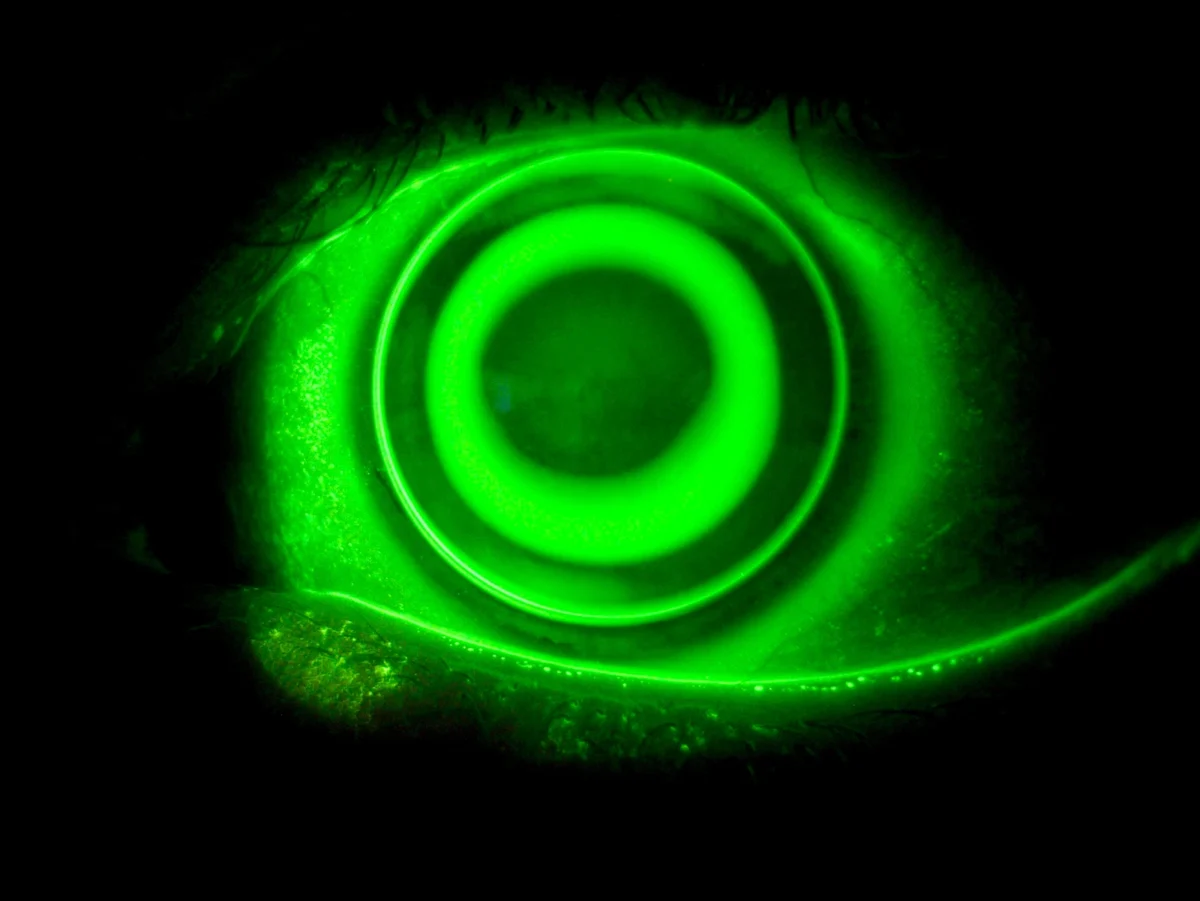

Lentes de contacto para córnea irregular

En casos de presentar corneas irregulares, debido a ectasias corneales y post cirugía refractiva, podemos adaptar lentes de contacto especiales con el objetivo de lograr una agudeza visual mayor y de mejor calidad para el paciente, de la que puede conseguir con el uso de gafas o lentes de contacto blandas convencionales.